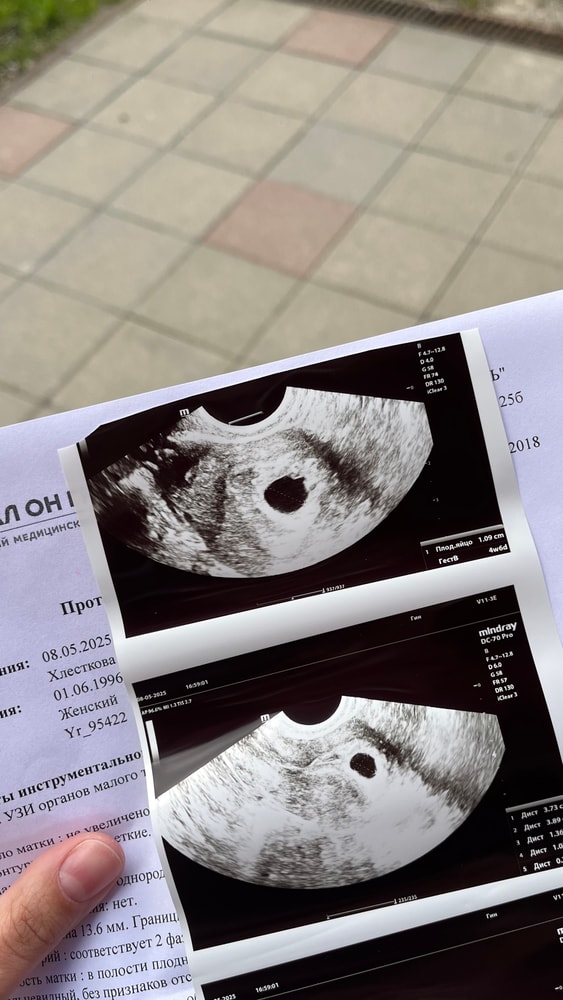

Ходила на 17ДПП(8 мая) в другую клинику, не в свою: нашли в матке ПЯ-10 мм, жм и эмбриона не было еще, но сказала, что зачатки жм есть и сказала, что ПЯ очень большое и на этом сроке должно быть видно все 😤

Поставила срок: 4 недели 6 дней

По месячным срок: 5 недель 2 дня, перенос был 21 апреля - наверное я рано пошла, но хотела убедится, что малыш на месте